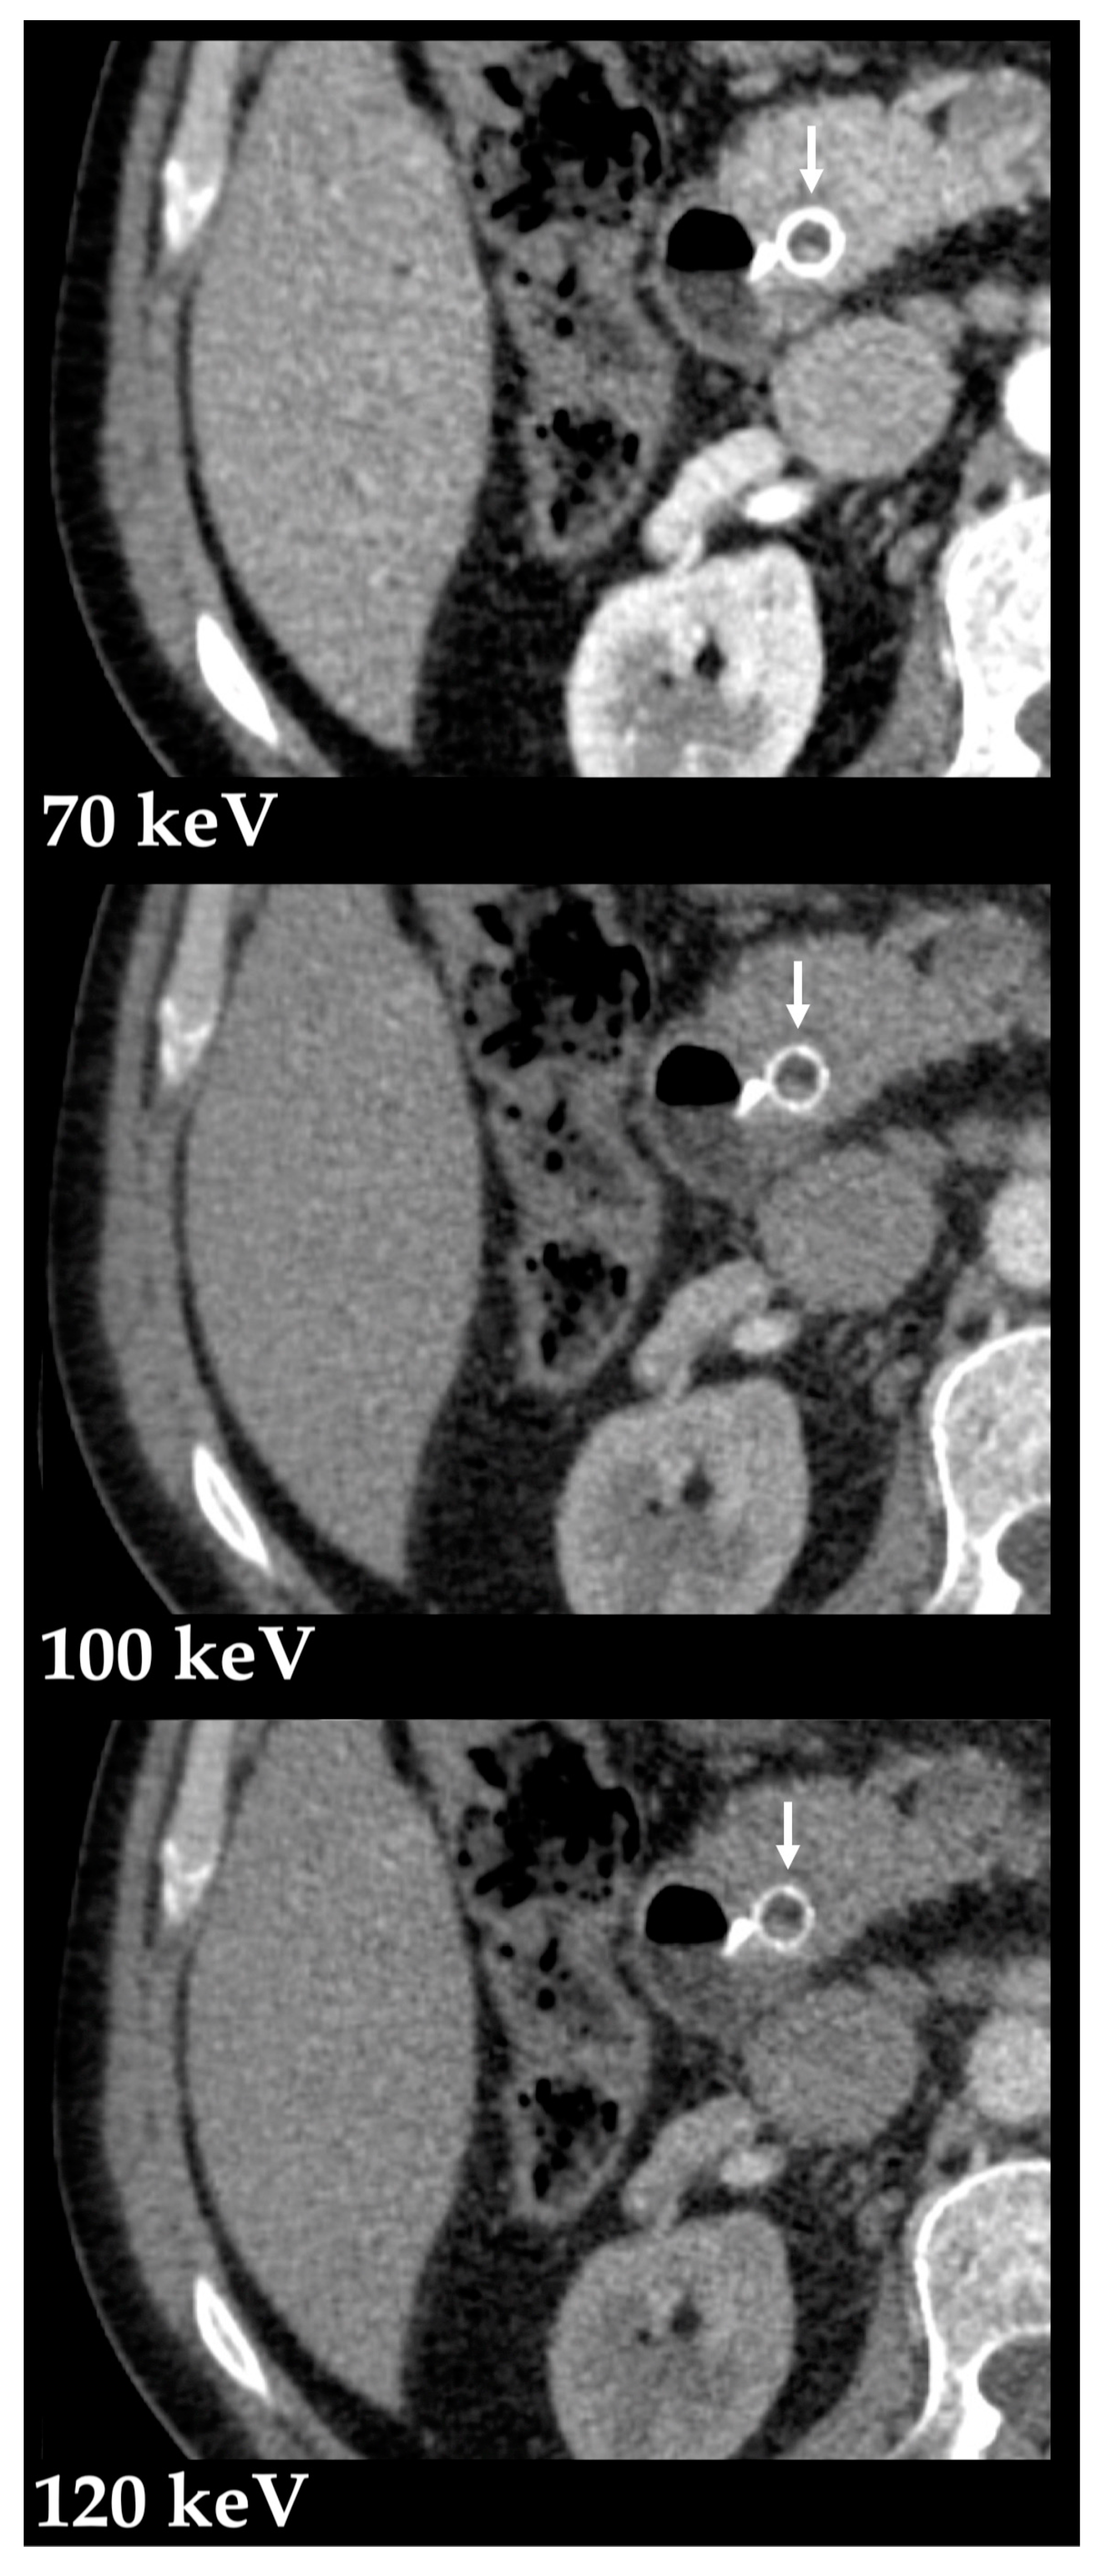

3.1. Postprocessing Techniques